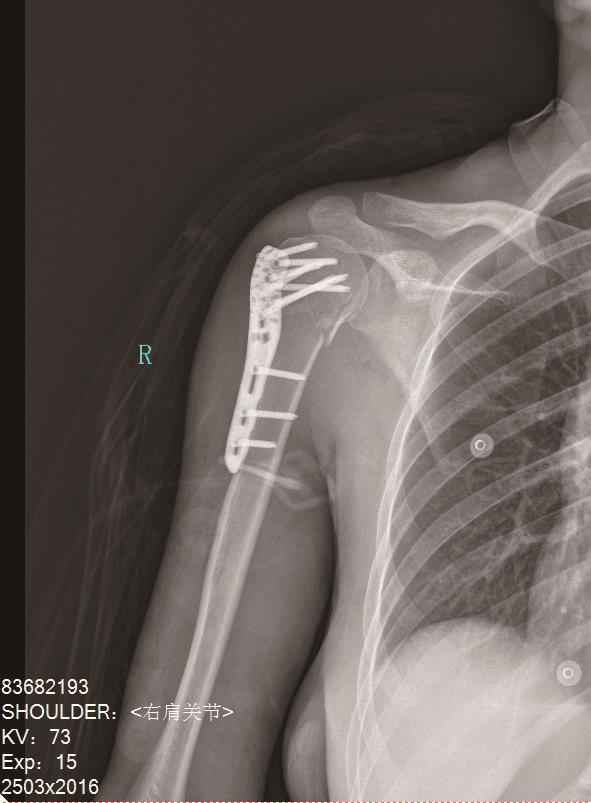

• 3D打印量化植骨辅助自体髂骨植骨联合锁定钢板内固定在老年肱骨近端粉碎性骨折中的疗效分析

2025, 35(19):92-98. DOI: 10.3969/j.issn.1005-8982.2025.19.015

摘要 (110) HTML (93) PDF 1.89 M (74) 评论 (0) 收藏

摘要:目的 探讨3D打印量化植骨辅助自体髂骨植骨联合锁定钢板(LCP)内固定在老年肱骨近端粉碎性骨折中的临床疗效。方法 选取2022年7月—2024年2月宝鸡高新医院收治的130例老年肱骨近端粉碎性骨折患者为研究对象。根据治疗方法的差异分为对照组与研究组。对照组采用自体髂骨植骨联合LCP内固定治疗;研究组在对照组基础上采用3D打印量化植骨辅助治疗。所有患者随访12个月,对比两组手术相关指标,比较两组患者术后6、12个月的肩关节功能、骨密度及生活质量,并记录随访期间并发症发生情况。结果 研究组较对照组出血量少,术后1 h疼痛评分低,手术时间、住院时间及骨折愈合时间均更短(P <0.05)。术后12个月两组的Constant-Murley评分、骨密度T值及SF-36评分均较术后6个月高(P <0.05)。研究组术后6、12个月的Constant-Murley评分、骨密度T值及SF-36评分均高于对照组(P <0.05)。研究组并发症总发生率低于对照组(P <0.05)。与对照组比较,研究组住院总费用和并发症处理费用均更低(P <0.05)。结论 在3D打印量化植骨技术的辅助下,对老年肱骨近端粉碎性骨折患者行自体髂骨植骨联合LCP内固定术可显著缩短手术时间,患者骨愈合更快、肩功能恢复更好,并降低并发症发生率。

• 0+1

• 1+1